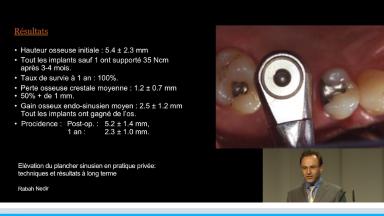

Une première étude dont le recul clinique atteint 10 ans, permet d’estimer le gain osseux obtenu autour de l’implant sans utilisation de biomatériaux, c'est-à-dire par simple soulèvement de la membrane sinusienne par les ostéotomes. Une deuxième étude au recul clinique de 3 ans présente une comparaison des gains osseux obtenus avec et sans utilisation de biomatériaux.